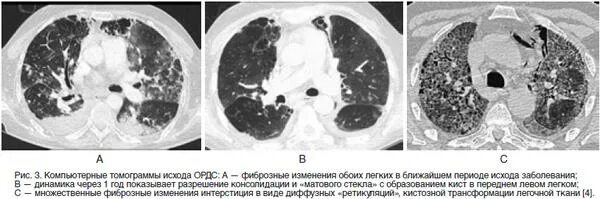

Ордс крипта